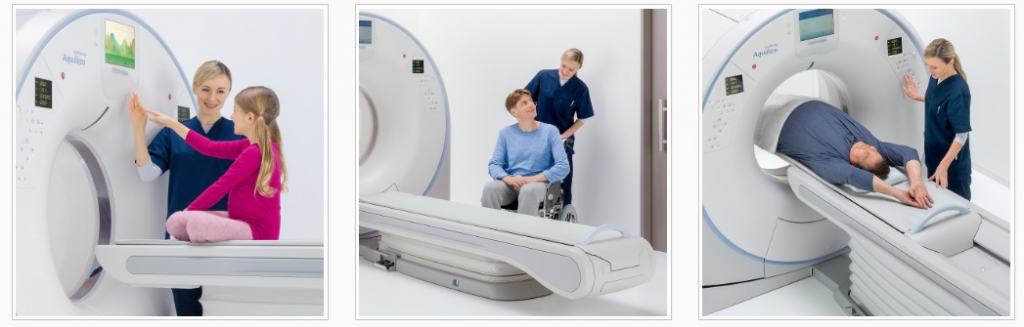

Система обеспечивает упорядоченный рабочий процесс от установки пациента до диагностики. Быстрое и эффективное обследование с автоматическим выбором дозы обеспечивает как оптимальные результаты визуализации, так и опыт пациента.

После регистрации пациента Aquilion Lightning автоматически выбирает правильные процедуры для взрослых или детей.

Быстрая и эффективная установка пациента

Гентри Aquilion Lightning предлагает инновационные разработки, улучшающие сканирование пациентов, обеспечивая при этом превосходную работоспособность и безопасность работы для техников.

Дисплей

Верхушка кушетки может быть опущена до минимальной высоты 312 мм для облегчения загрузки и переноски пациента с инвалидной коляски или кровати.

Техническая помощь по боковым слайдам

Технология Assist Lateral Slide * обеспечивает безопасность и комфорт, обеспечивая моторизованное позиционирование пациента, снижая риск травмы пациента и технолога.